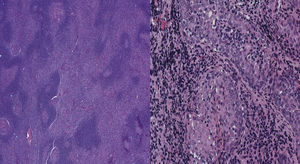

Case 2A 16-year-old boy presented with intermittent painless cervical lymphadenopathy and bilateral parotid swelling for more than 5 years. Neck CT demonstrated enlargement of the parotids. A fine needle aspiration showed a benign lymphoid tissue with no evidence of malignancy. Laboratory data showed an increased ESR (122mm/h). Histopathology analysis showed infiltration of the salivary gland by a lymphocytic proliferation forming confluent nodular masses and follicular hyperplasia of the attached lymph nodes, indicative of a lymphoid malignancy (Fig. 1). Immunohistochemical stains demonstrated sheets of CD20+ B cells that were negative for CD5, CD43, and cyclin-D1, confirming B-cell clonal proliferation (Fig. 2). CD10 and BCL-6 stains highlighted germinal centers which were negative for BCL-2. A Ki-67 stain showed numerous positive cells within and between germinal centers (20–30% cells). Parotidectomy and radiotherapy was performed. Serologic testing revealed only a remote infection by CMV and EBV. Immunological tests showed positive RF, ANA, anti-SSA and anti-SSB antibodies. Despite only vague sicca symptoms, ophthalmology exam revealed corneal and conjunctival erosions, and the diagnosis of SS was made. Hydroxychloroquine and rituximab were started. There was no evidence of tumor recurrence after >14 months follow-up.

The occurrence of lymphoma in SS is extremely rare in childhood. EMZL is a low-grade lymphoma that usually occurs in the setting of a benign myoepithelial sialadenitis (MESA) and biopsy confirms the diagnosis. Clonal expansion to EMZL is believed to be triggered by chronic immune stimulation in the context of a preexisting inflammatory response from autoimmune diseases or chronic infections, amyloidosis, some translocations and common variable immunodeficiency.6–9 Differences in Rituximab response might be a higher pretreatment number of CD20+ B cells/mm2 parotid gland parenchyma.10